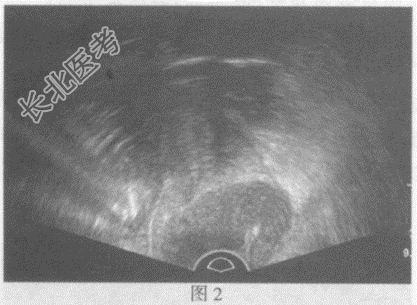

- 单项选择题临床资料:女性患者, 32岁,自述不规则阴道出血半月余。超声综合描述: (图1经腹扫查;图2、彩图经阴道扫查)子宫颈形态失常, 宫颈后唇可见低回声区,边界尚清晰, 形态规则,向外突起, CDFI:其内可见丰富动静脉血流信号。